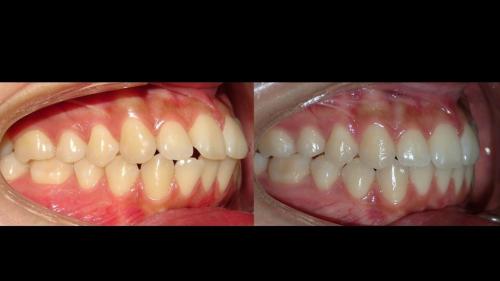

large-Resultados sin que se note ortodoncia

large-Resultados con balance

large-Ortodoncia Lingual

large-Resultado de avance de la mandibula

large-Ortodoncia lingual invisible

large-Lingual

large-Fractura con resina

large-Fractura

large-Combinacion con cirugia

large-Diapositiva14

large-Cambios en el perfil

large-Cambio magico

large-Cambio labial

large-Cambio en el perfil

large-Adultos -Se puede

large-Avance de mordida

large-Sonrisa en adulto

large-Sonrisa Adulto